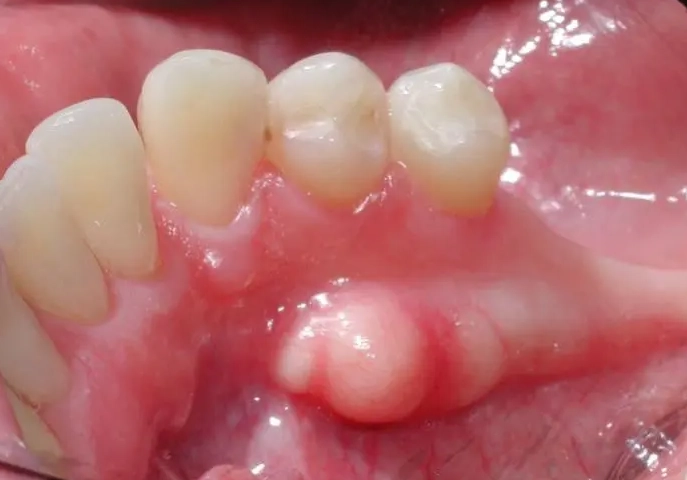

Fibroma

This is the body's overzealous response to chronic irritation. If you have a habit of chewing on your cheek, a rough tooth, or an ill-fitting denture rubbing in the same spot, your body might lay down extra fibrous tissue as a “callus.” The result is a fibroma. What it feels/looks like: A firm, smooth, pink lump. It's like a little dome-shaped knot of scar tissue. It's anchored down and doesn't move much when you push it. Completely benign and very, very common.

| Fibroma | Inner cheek, tongue, gums (sites of friction) | Firm, smooth, pink, dome-shaped | Reaction to chronic irritation; feels like a scar. |